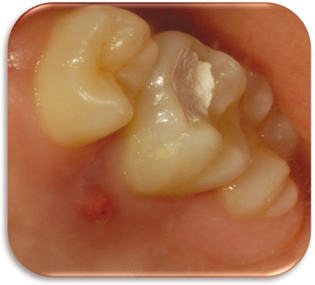

Figure 1

Pre-operative clinical photo.

Figure 1 Pre-operative clinical photo.